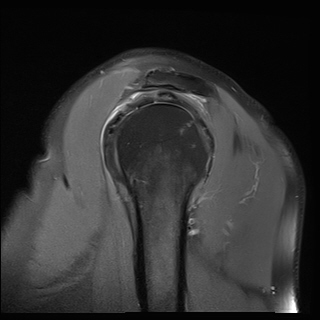

±Ø»ó°Ç ¿ÜÃø Á¾´Ü¸é°Ë»ç ½Ã Á¡¾×³¶ ºÎÁ¾ÀÌ °üÂûµÊ(±×¸² 4).

±Ø»ó°Ç ÆÄ¿­, Á¡¾×³¶¿°, °ßºÀÇÏ °ñ±Ø